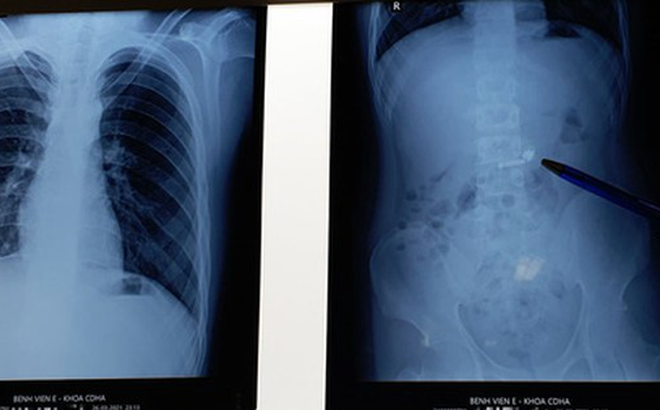

Kết quả chụp X-quang tại bệnh viện cho thấy trong ổ bụng bệnh nhân có h́nh tai nghe điện thoại không dây. Đáng nói, bệnh nhi là trẻ tự kỷ nên việc điều trị không dễ dàng. Bệnh nhân không hợp tác với các thầy thuốc trong việc lấy máu làm xét nghiệm, chiếu chụp và gây mê... Phải gần 4 tiếng sau vào viện, bác sĩ mới tiến hành nội soi để gắp dị vật cho bệnh nhân.

Chiếc tai nghe không dây nằm trong ổ bụng thiếu niên ở Hà Nội - Ảnh: Bệnh viện cung cấp

Bệnh nhi may mắn khi nuốt phải dị vật là h́nh dạng tṛn, trơn bóng nên đă trôi xuống dạ dày mà không bị mắc lại ở vị trí thực quản hay đường thở, tránh được nhiều biến chứng nguy hiểm.